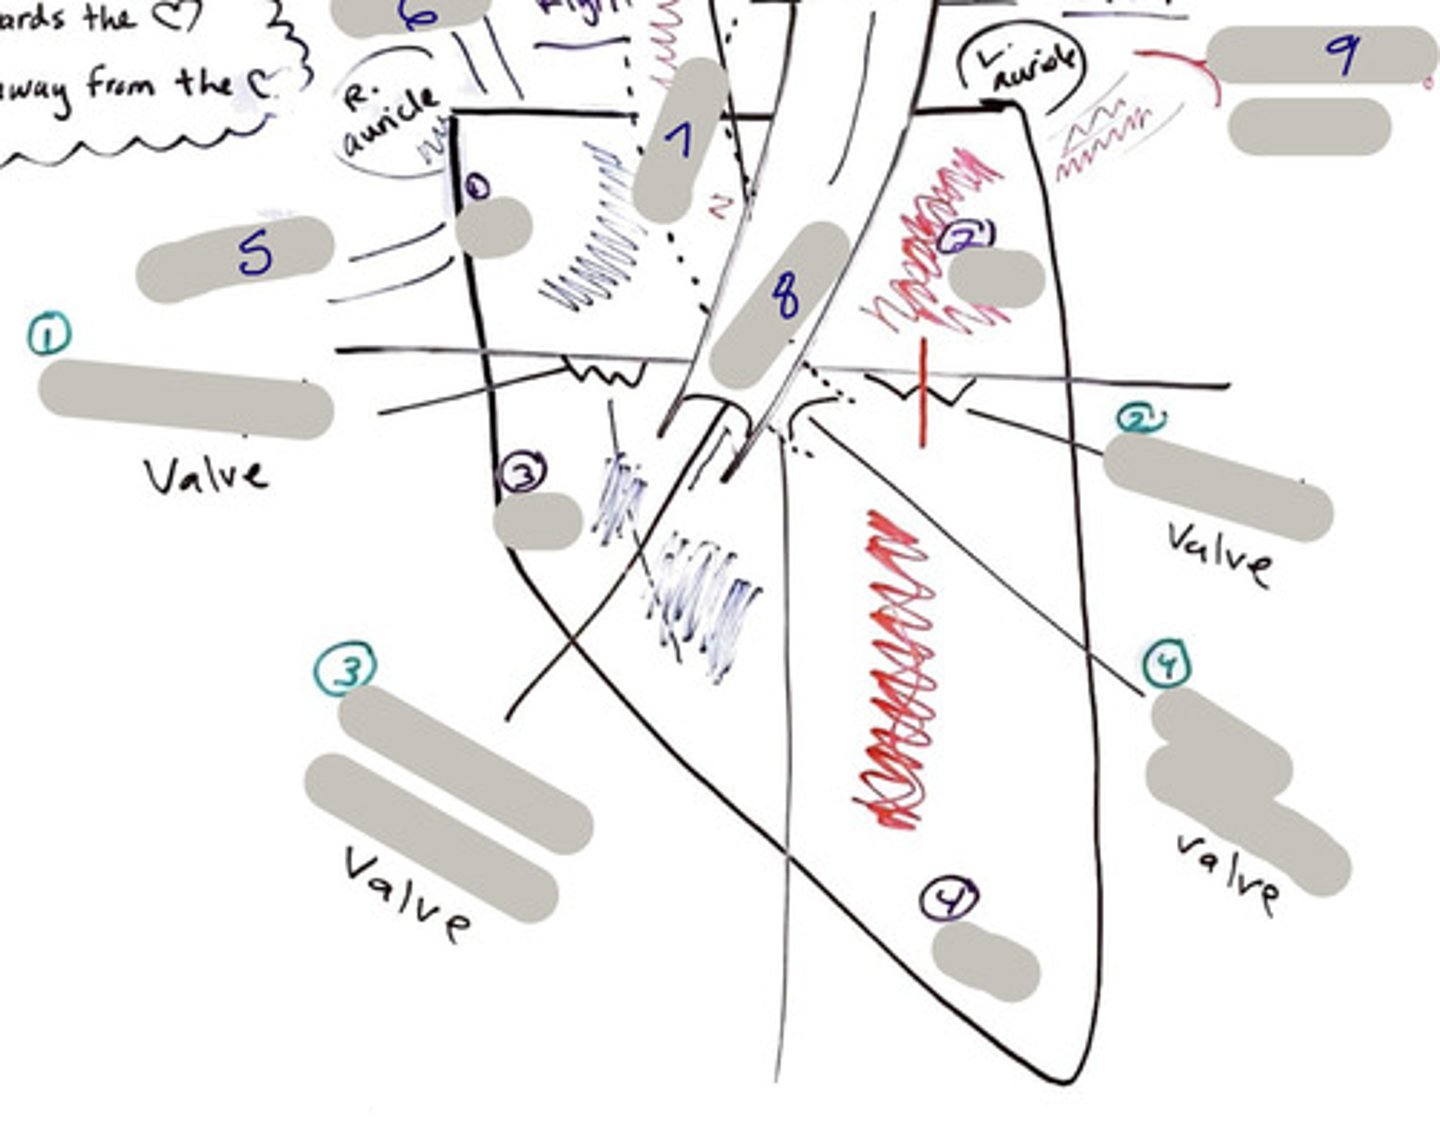

Tricuspid Valve (Right Atrioventricular Valve)

1-valve

Bicuspid valve (Left Atrioventricular Valve)

2-valve

Pulmonary Semilunar Valve

3-valve

Aortic Semilunar Valve

4-valve

Right Atrium

1-chamber

Left Atrium

2-chamber

Right Ventricle

3-chamber

Left Ventricle

4-chamber

Inferior Vena Cava

5-A vein that is the largest vein in the human body and returns blood to the right atrium of the heart from bodily parts below the diaphragm.

Superior Vena Cava

6-A vein that is the second largest vein in the human body and returns blood to the right atrium of the heart from the upper half of the body.

Aorta

7-The large arterial trunk that carries blood from the heart to be distributed by branch arteries through the body.

Pulmonary Trunk

8-carries blood from right ventricle to pulmonary arteries

Pulmonary veins

9-a vein carrying oxygenated blood from the lungs to the left atrium of the heart.